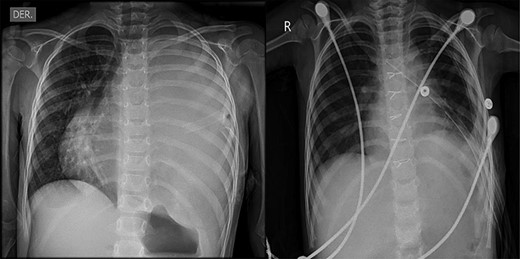

(A) Preoperative chest X-ray showing total atelectasis of the left lung and deviation of the cardiac silhouette to the right. (B) CT scan showing deviation of the cardiac silhouette to the right. (C) Heterogenic density tumor multiloculated of the left hemithorax, which probably originated in the mediastinum and extended to the whole left pleural space with displacement of the mediastinum to the right

A 4-year-old female with complete vaccines and without prior pathological prenatal history was admitted and transferred with a diagnosis of pleural effusion from a primary health center where a thoracic drainage tube was placed. She presented a 1-month history of progressive cough, fever and dyspnea. The physical exam was relevant for thoracic asymmetry, diminished breath sounds and vocal vibrations in the left hemithorax. A chest X-ray showed a total occlusion of the left hemithorax with deviation of the mediastinum to the right side. A computed tomography (CT) scan showed pectus excavatum and the presence of a large multiloculated mediastinal mass extending to the left pleural space (Fig. 1). The mass was heterogeneous containing soft tissue elements, cystic areas and calcification. Laboratory workup was remarkable for mild anemia (hemoglobin 10.2 g/dl), eosinophilia (5.2 cells × 109/l) and elevated alkaline phosphatase. α-Fetoprotein (AFP) and β-human chorionic gonadotropin (β-hCG) were both normal; cancer antigen-125 (CA-125) was elevated (83.3 UI/ml, normal <46 U/ml). Initial assessment suggested benign teratoma.

(A) Preoperative chest X-ray showing total atelectasis of the left lung and deviation of the cardiac silhouette to the right. (B) Postoperative Day 9 chest X-ray after total resection of the teratoma, showing re-expansion of the left lung